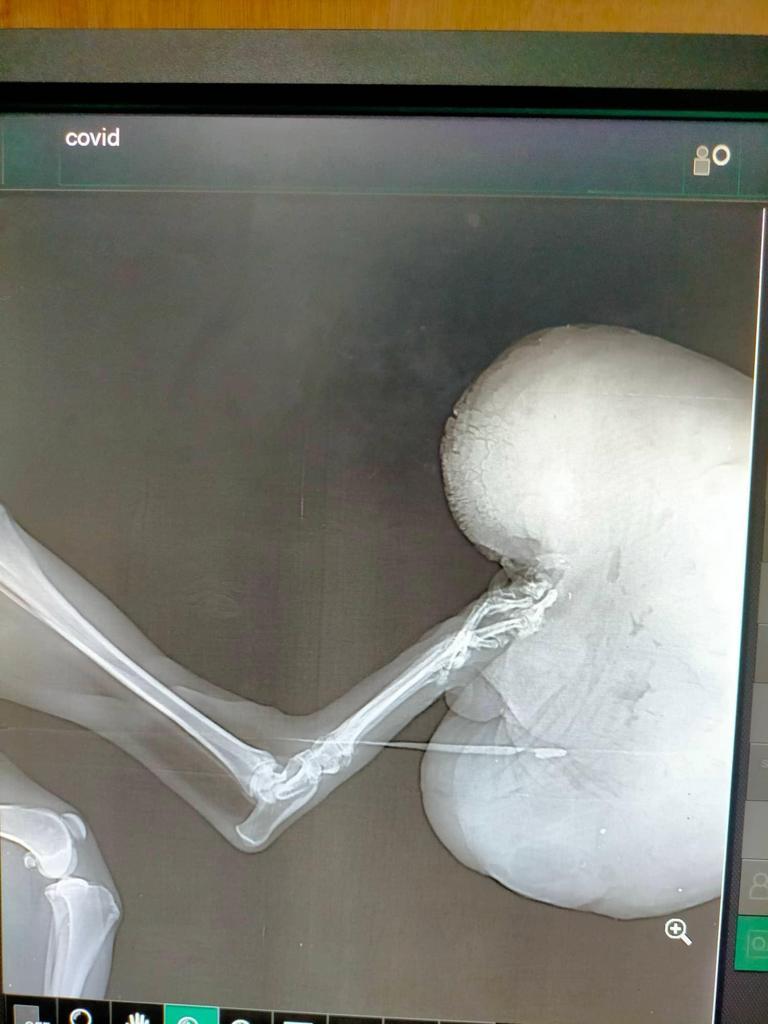

A concerned Filipino animal lover sent a message to the clinic asking for help for this dog with a huge tumor hanging from his paw. Knowing that this type of tumor could even get larger, and realizing that the dog had been suffering for so long carrying this heavy burden, he organized the only rescue he could afford - which is, no less no more, taking the dog away.

It wasn't easy to find the dog, but it turned out he had an owner. Jun, the rescuer, managed to locate the family and learned that the dog, named Kai, was 4 years old. They took him to the clinic, but the vet refused to operate because the dog was too thin to handle the operation.

Kai is still boney and his owner is undecided about further actions. He wants to remove Kai’s tumor, but he doesn’t have the funds for the operation. The family is also afraid of the risk of losing Kai if the operation fails. One thing is certain - Kai will not survive without this surgery.

There is no doubt that the tumor needs to be removed. Although Kai was tested negative for distemper, he is positive for ehrlichia. He has high infection, anemia, and a moderately low platelet count. He has possible pancreatitis and is very very stressed - probably also due to severe tumor. He also has an infection of his burdened liver.

Most of these things are caused by the very existence of the tumor, hence the need for very urgent and expensive surgery. Of course complications may arise, we cannot rule this out... But the tumor will only grow bigger and more painful.